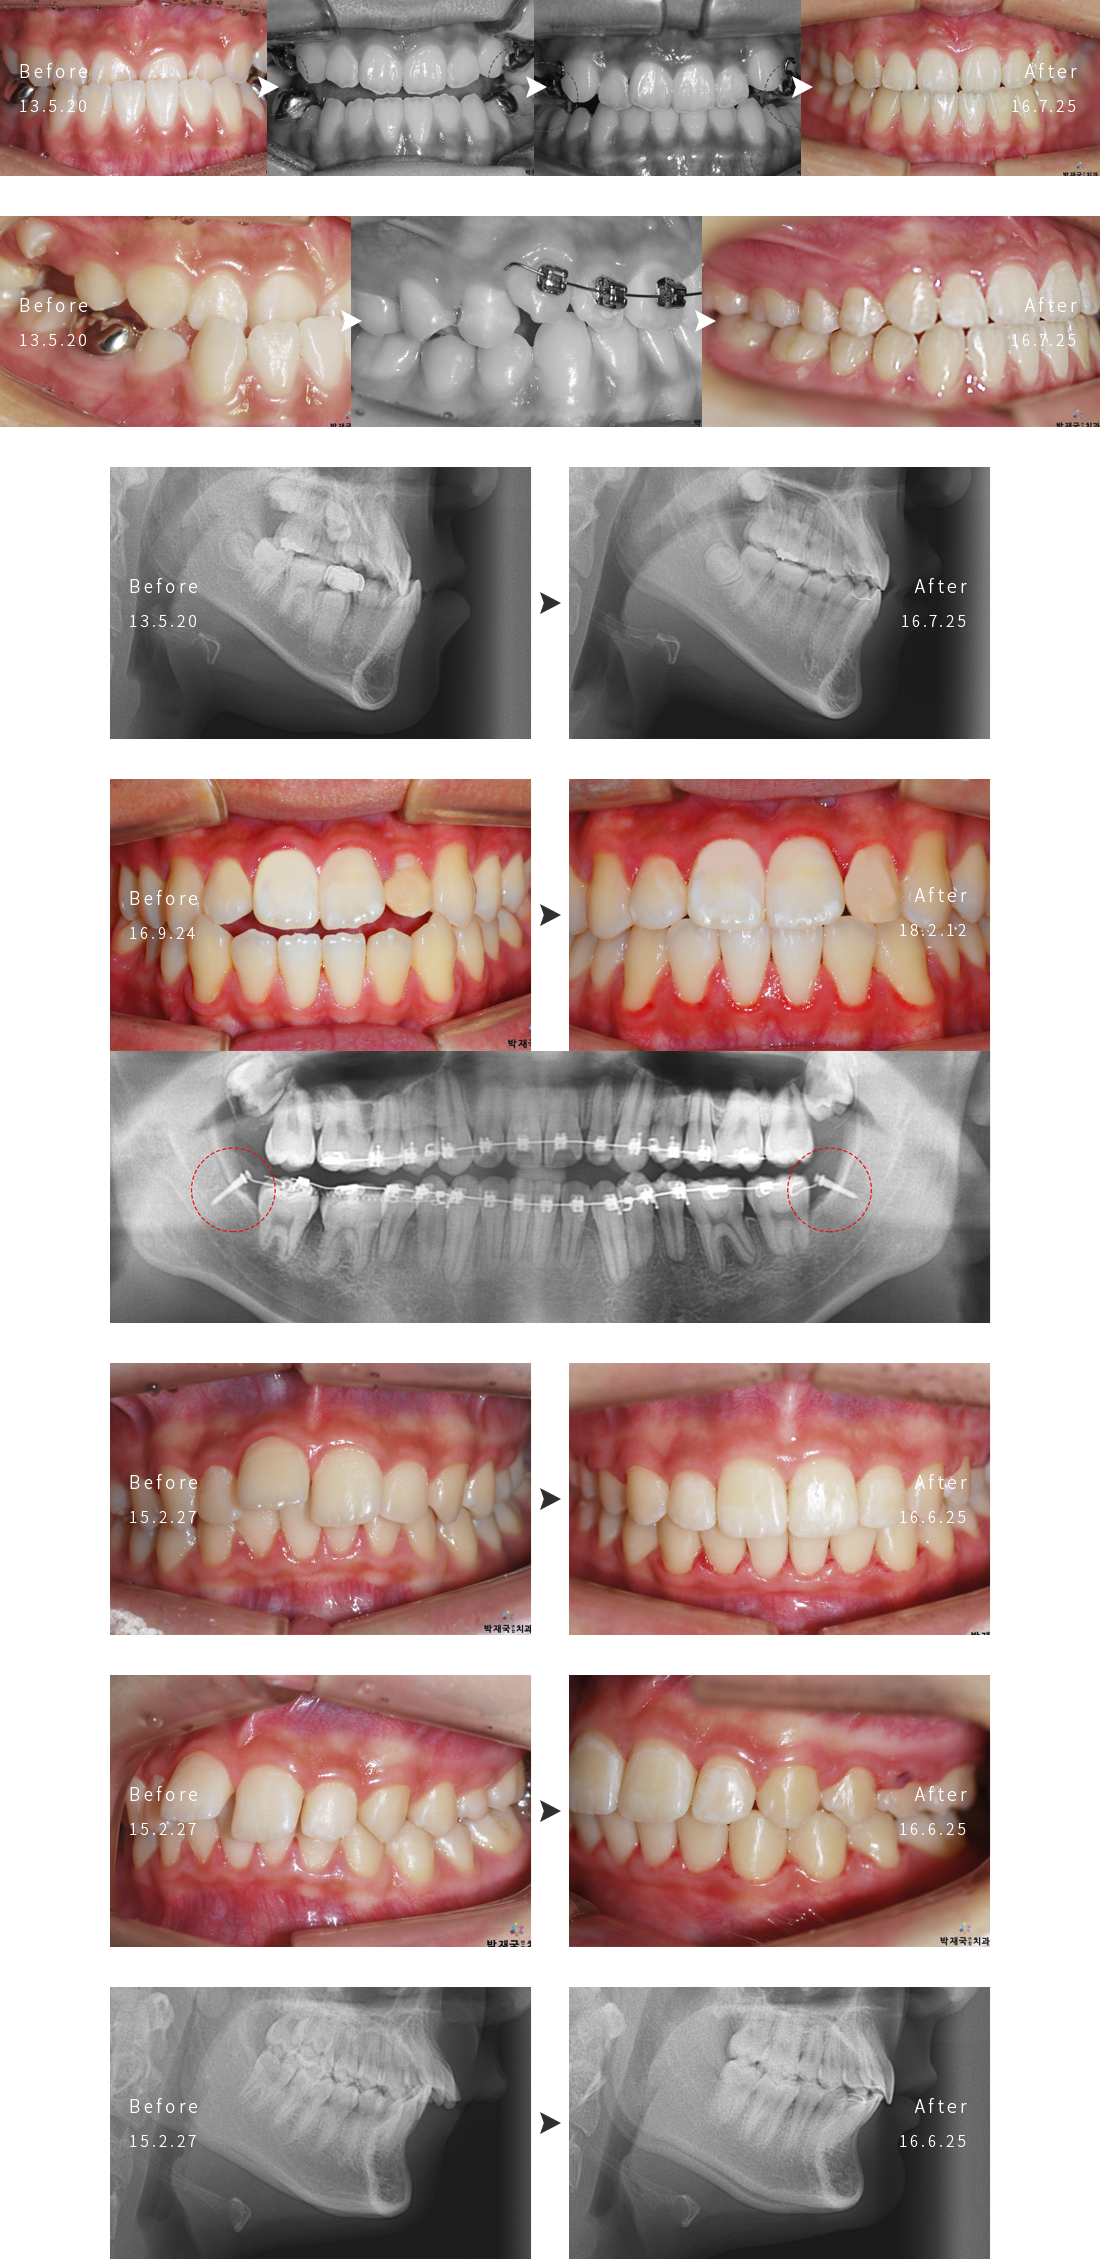

ÁÖ°ÆÅα³Á¤ ±³Á¤ »ç·Ê

orthodontic Clinic